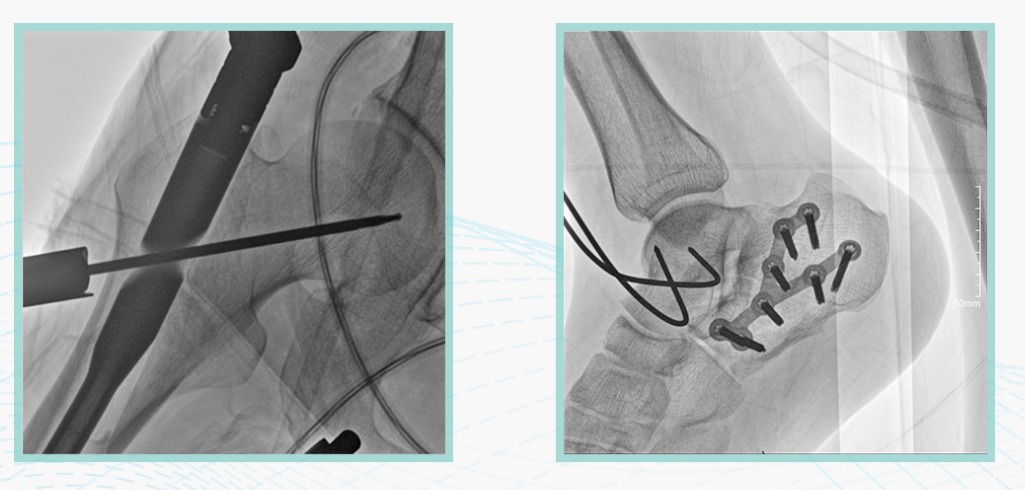

安健科技悅畫移動C臂X線攝影系統,采用了業內技術最尖端的CMOS探測器。基于性能優異的針狀CSI閃爍體涂層和高靈敏度的CMOS感光芯片,悅畫可以實現在超低X線劑量條件下實現高清晰影像成像,相較于一般的影增移動C臂和平板C臂,動態范圍更高,影像的層次感和對比度更好。

在產品的性能參數設計上,悅畫的像素可達到200萬,空間分辨率可達到3.2線對,采用16bit的影像灰度,悅畫在影像后處理上,通過SPI金字塔圖像算法,支持攝影、脈沖透視影像、連續透視等多種模式下的影像采集,動態透視影像視頻支持保存與回放。雙大屏的設計,透視影像支持三檔放大,保證臨床影像讀取的便利。

悅畫在影像的偽影處理上,也積累多項圖像處理專利技術。通過對植入物的精準識別,悅畫能夠精準祛除植入物偽影與運動偽影,保證高質量的影像輸出,無論是影像的對比度、分辨率(清晰度)相較于市面上的移動C臂產品都更勝一籌。